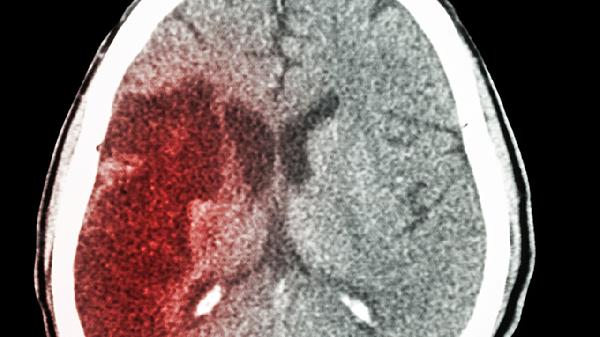

脑积水患者除规范用药外,需保持头部抬高30度卧位,避免剧烈咳嗽和用力排便。饮食宜选择低盐、高蛋白食物,如鸡蛋羹、清蒸鱼肉等,每日饮水量控制在1500毫升以内。定期进行头颅CT或MRI复查,观察脑室变化情况。若药物控制效果不佳,可能需考虑脑室腹腔分流术等外科干预。